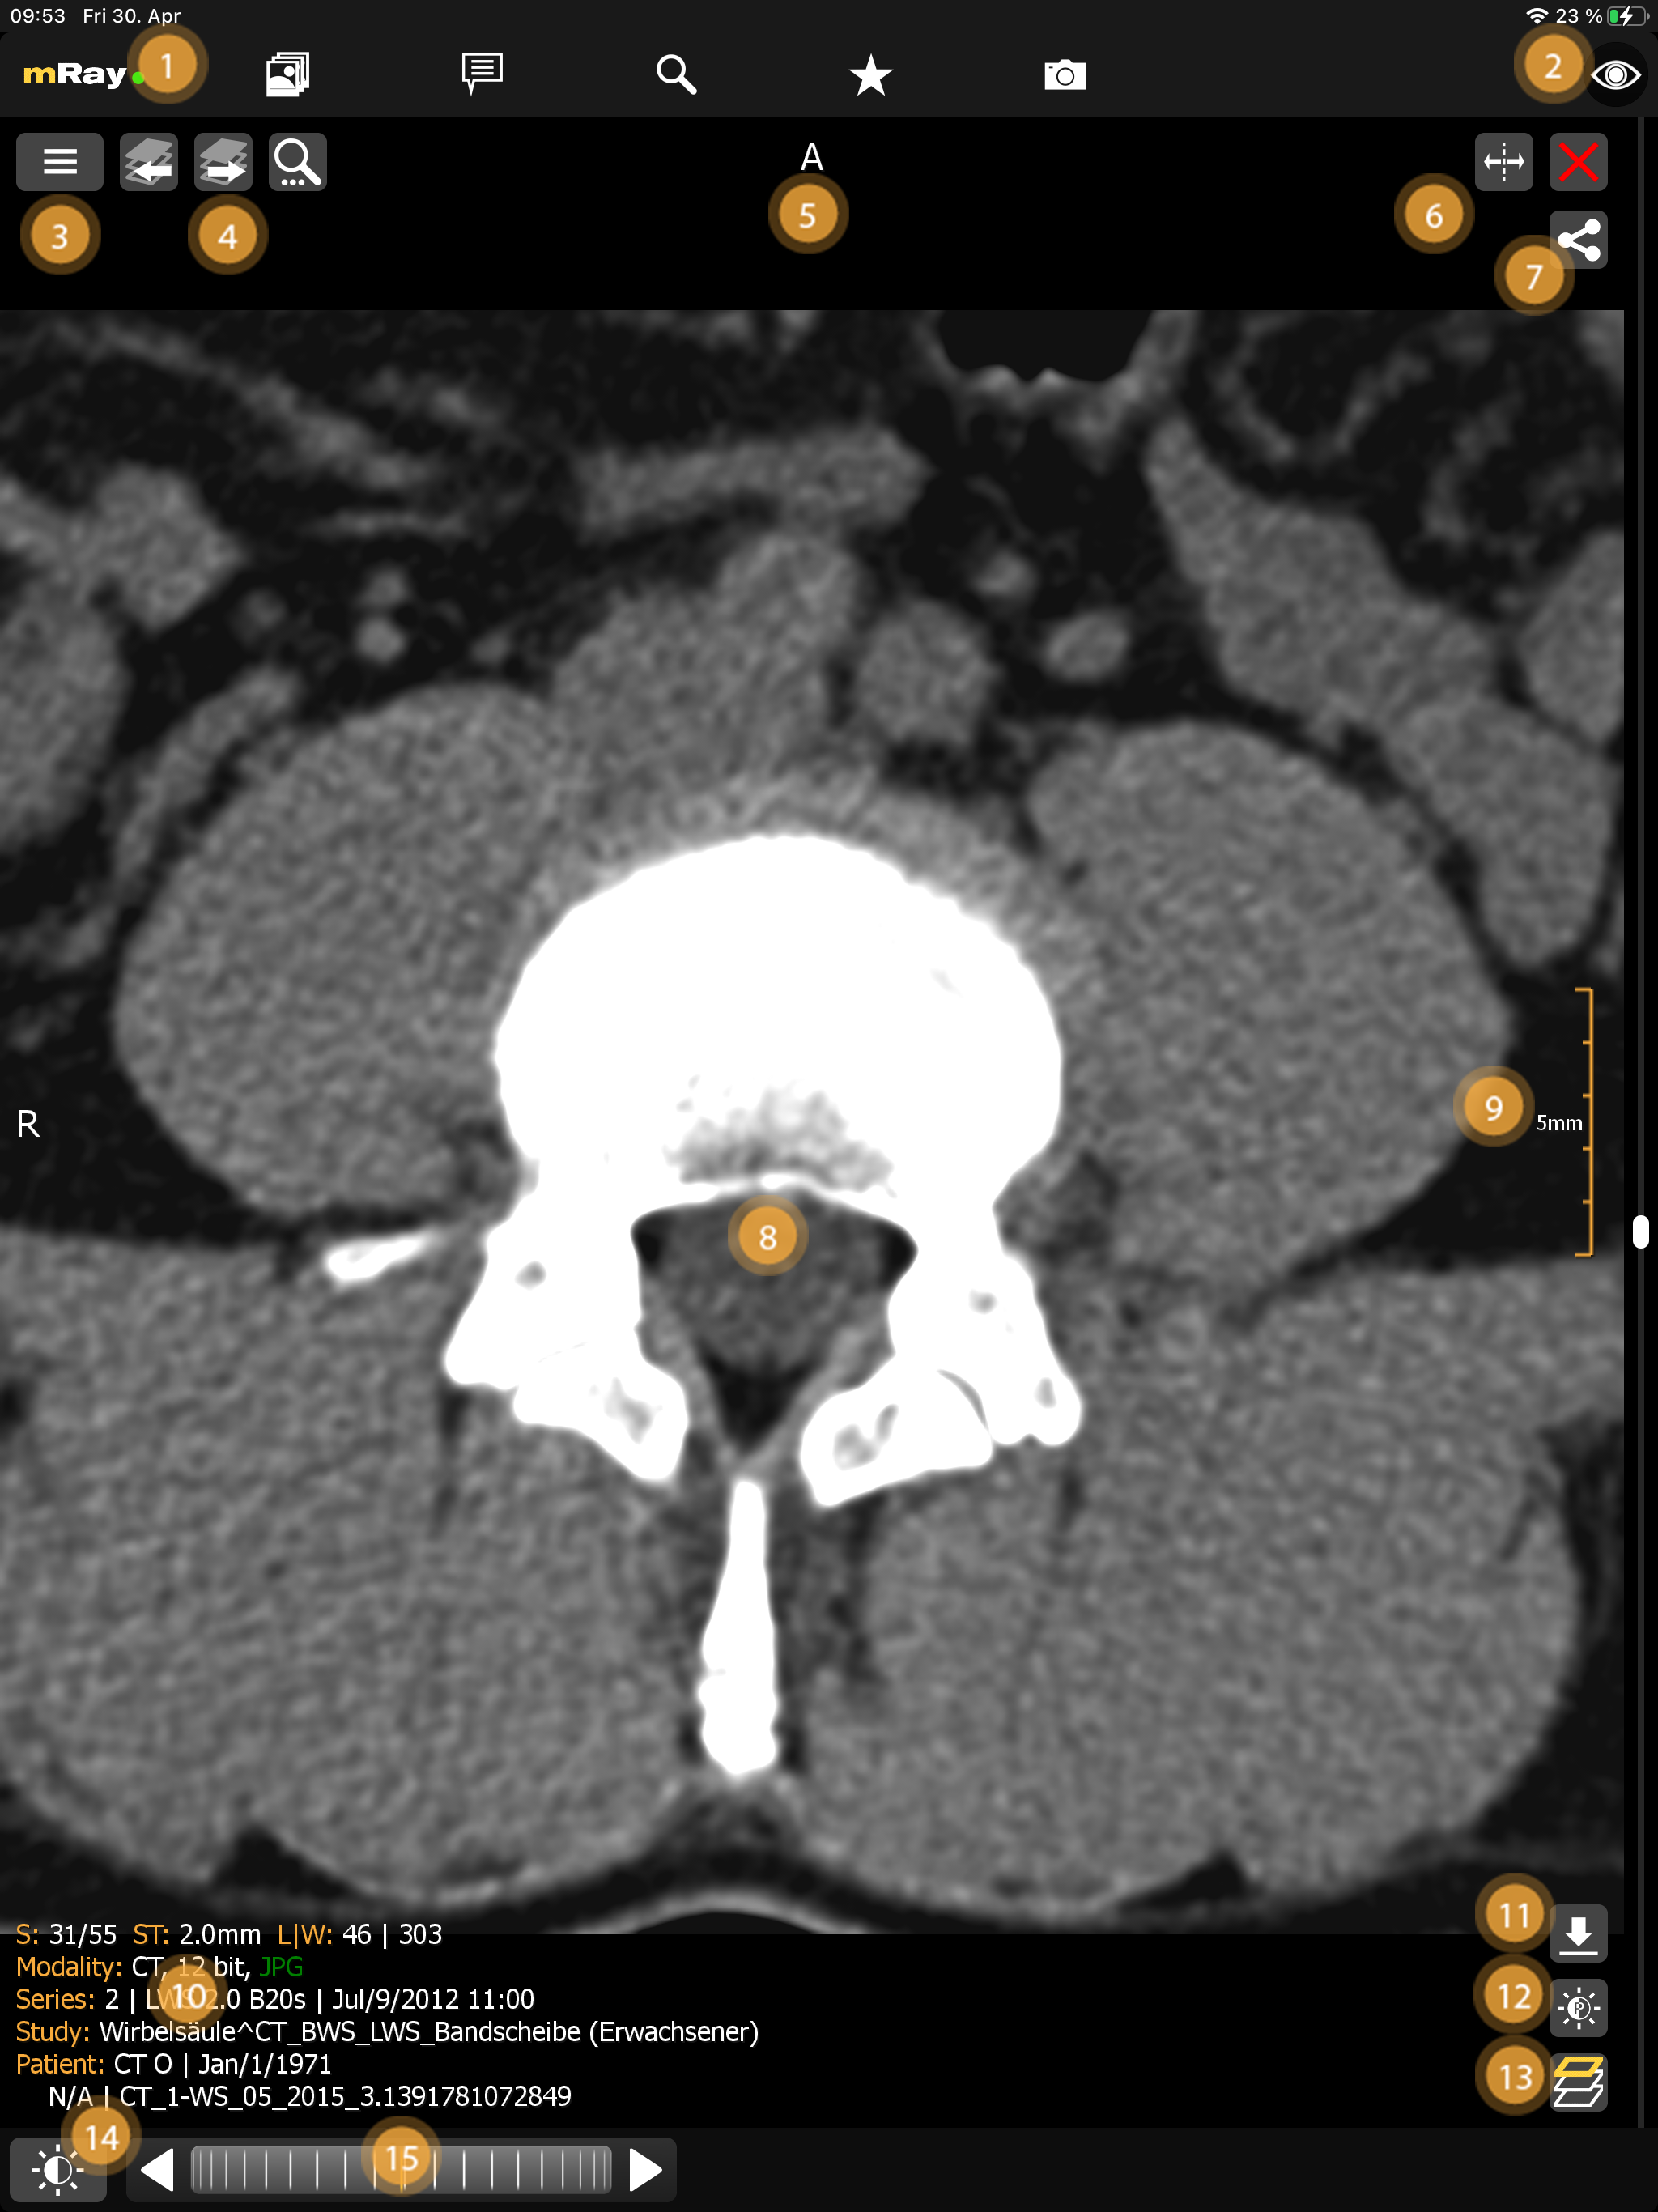

10. Viewer

Selecting a series from the Inbox will open the viewer.

The following functionality is available:

-

Open the Main menu and keep an eye on the connection to the server via the traffic light system.

-

Toggle-information-button switches between different modes for the information overlay:

-

All information: display all user-controls and meta-data for the current dataset.

-

Minimal information: only display the patient name and the image-orientation

-

No information: only display the imagedata.

-

-

Go to Series selection via this button.

-

Switch to the previous or next series within the study, in case there is more than one series available.

-

Shows together with the sign on the left edge of the screen the orientation of the image by the view of a patient. The directions will be determined like in the following (combinations possible):

-

R - Right: The direction in which X decreases.

-

L - Left: The direction in which X increases.

-

A - Anterior: The direction in which Y decreases.

-

P - Posterior: The direction in which Y increases.

-

I - Inferior: The direction in which Z decreases.

-

S - Superior: The direction in which Z increases.

-

-

Split button and close buttons to manage multiple views (up to 2 on smartphones, 4 on tablets).

-

The "Close"-Button moves the viewer to the background.

-

The view shows the image data. The tools (12) allow you to interact and adjust the image. You can always use the two fingers to zoom in/out, except of you turned on 1:n zoom.

-

The measurement shows the scaling of the image. Notice that the displayed number of length shows the inner length of the measure. In this case the total length of the measure is 25 mm, as every step is 5 mm long.

-

Information about the patient, study, modality and other. The following abbreviations are used:

-

S: information about the current slice position and number of slices.

-

ST: information about the slice-thickness

-

L|W: information about the current level-window settings.

-

IN: the DICOM Instance Number.

-

-

Download the current dataset as DICOM Data (only if enabled on this server)

-

Adjust level window presets with the 'Level-Window'-Button.

-

'MPR-modality'-button to change the view modality.

-

Opens the tool and interaction menu.

-

The scrollwheel allows the user to scroll through a series (see Interactionbar). The scrollbar on the right edge of the screen can also be used to scroll through a series with only one hand (see Scrollbar).